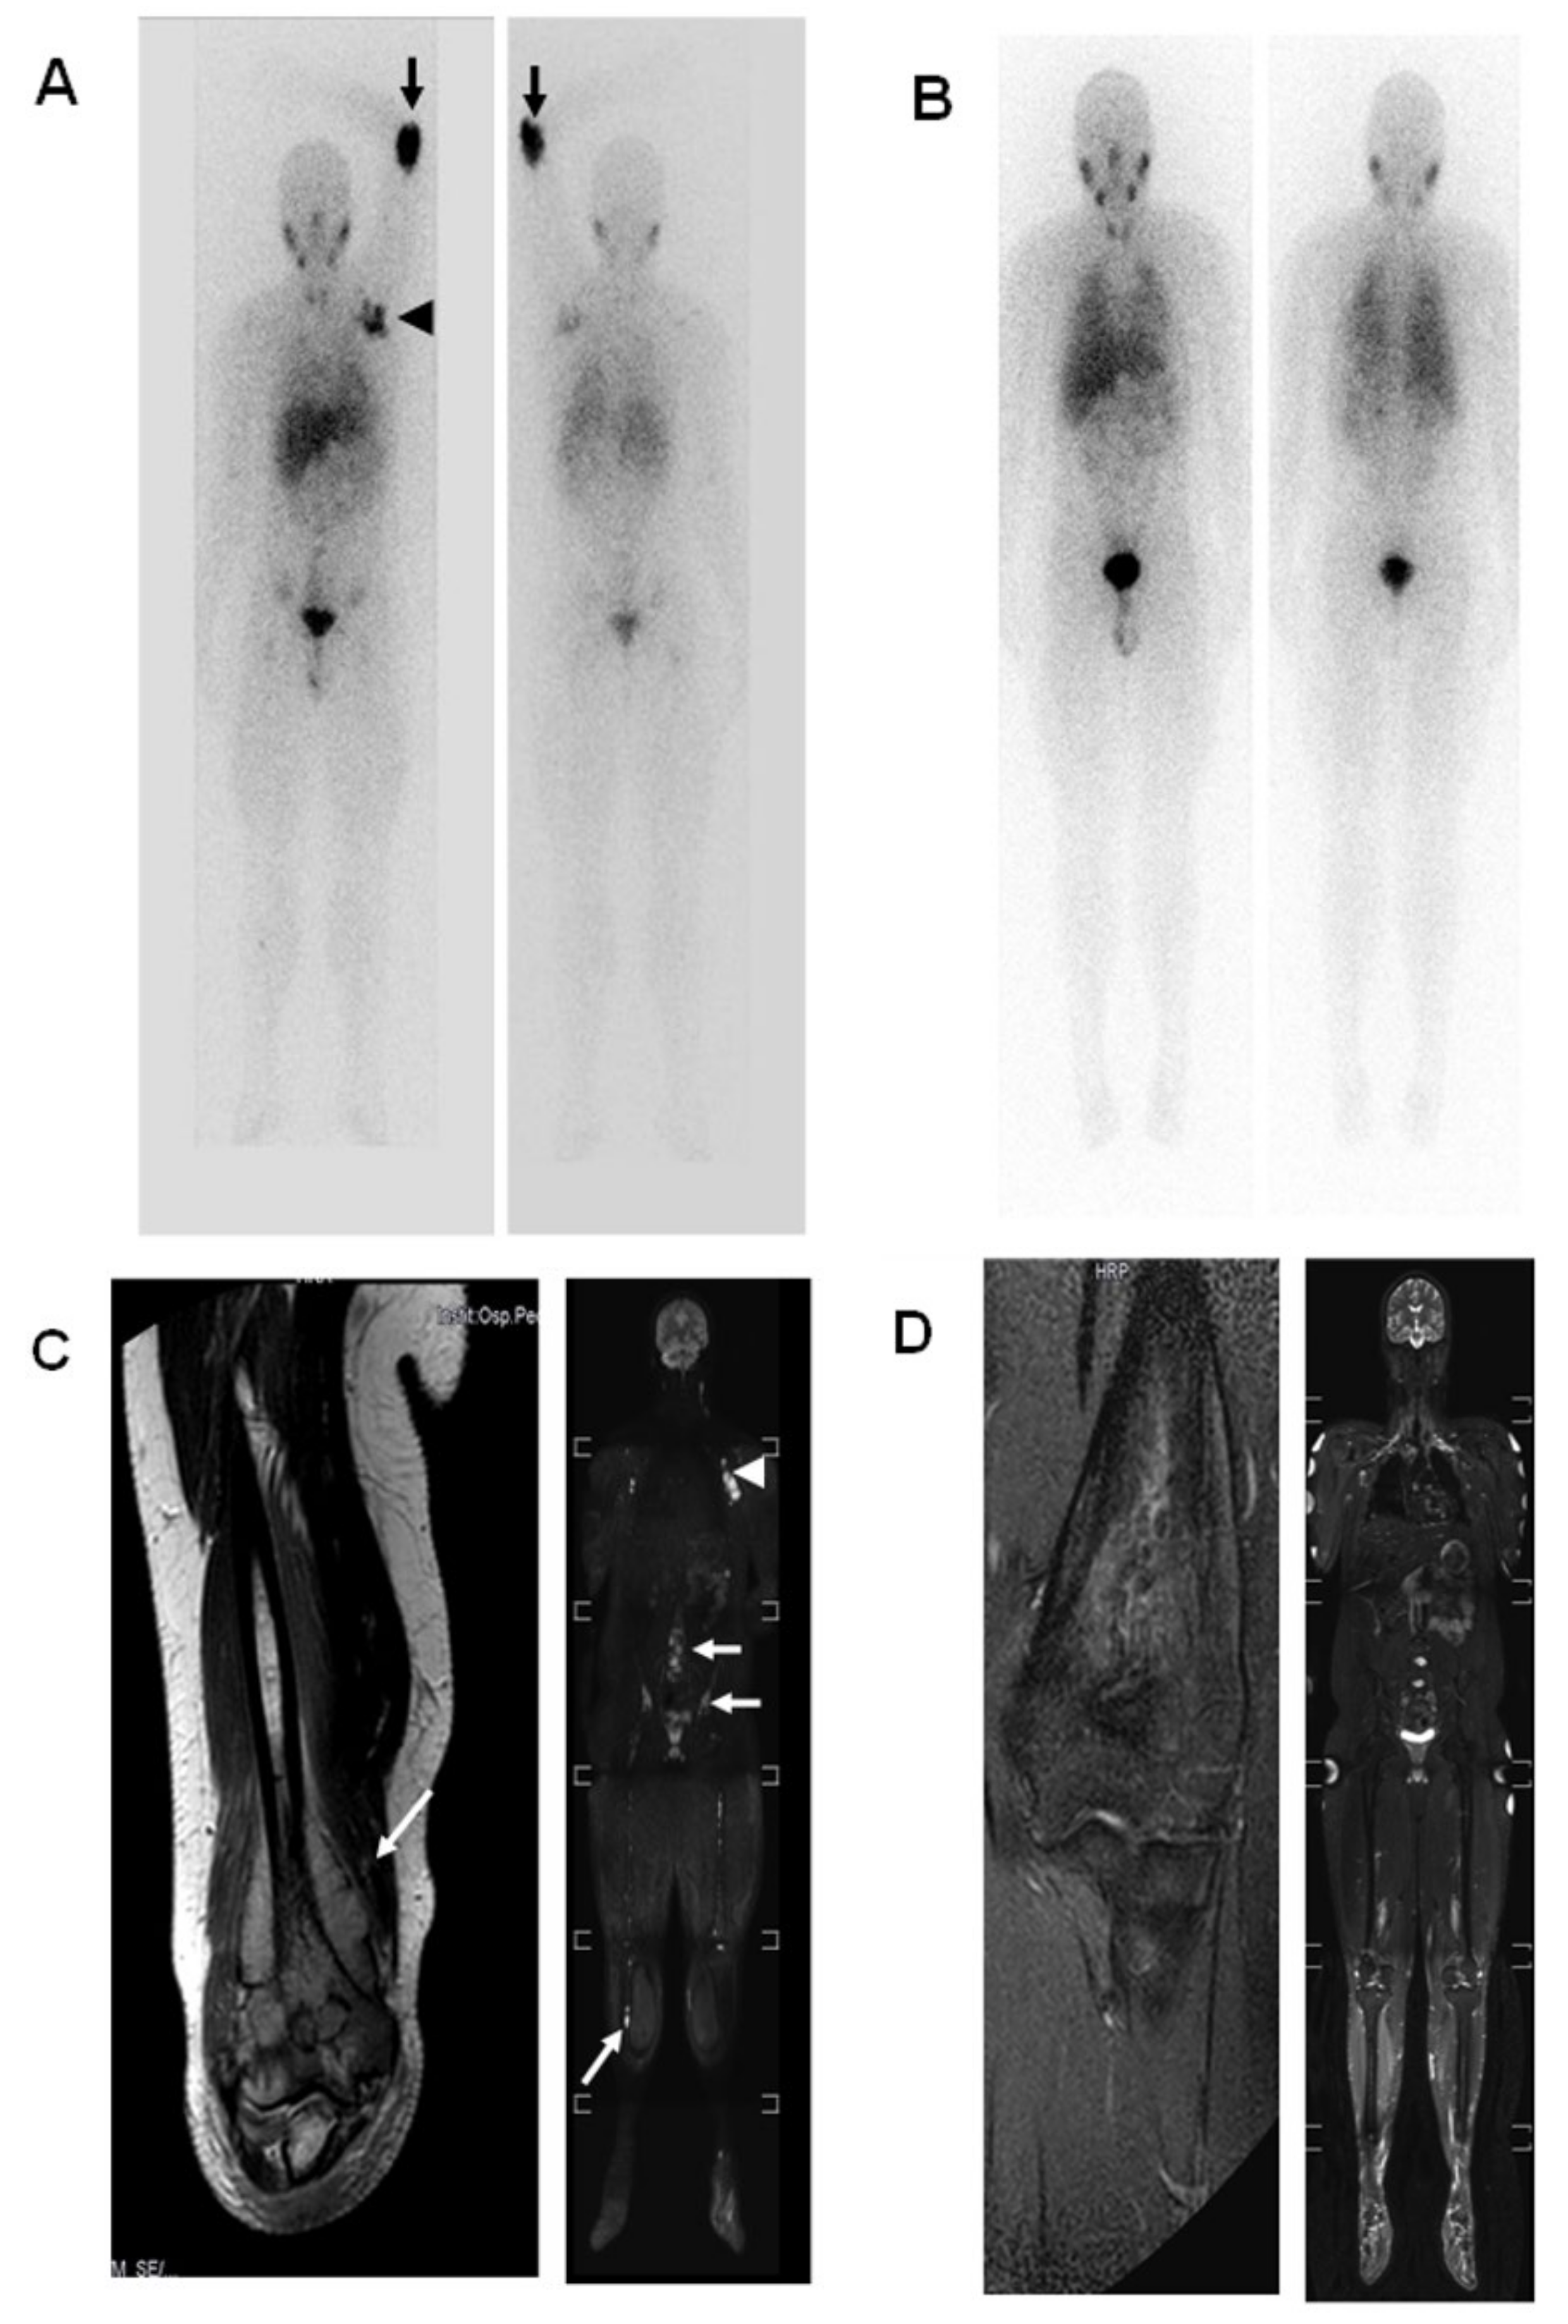

2.2. Case 2

- Berlanga, P.; Pasqualini, C.; Pötschger, U.; Sangüesa, C.; Castellani, M.R.; Cañete, A.; Luksch, R.; Elliot, M.; Schreier, G.; Kropf, M.; et al. Central nervous system relapse in high-risk stage 4 neuroblastoma: The HR-NBL1/SIOPEN trial experience. Eur. J. Cancer 2021, 144, 1–8. [Google Scholar] [CrossRef]

- DuBois, S.G.; Kalika, Y.; Lukens, J.N.; Brodeur, G.M.; Seeger, R.C.; Atkinson, J.B.; Haase, G.M.; Black, C.T.; Perez, C.; Shimada, H.; et al. Metastatic sites in stage IV and IVS neuroblastoma correlate with age, tumor biology, and survival. J. Pediatric Hematol. Oncol. 1999, 21, 181–189. [Google Scholar] [CrossRef]